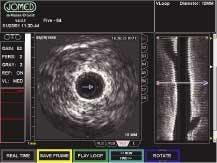

The frame-grabber data are transferred via a Coreco Sapera API software interface to another Viper-RGB frame grabber and then on to an In-Vision application board. The Sapera software library offers more than 300 image-acquisition, processing, and analysis functions. The application board transfers the fluoroscopic data via Sapera's DirectDraw software to the system's video memory and 17-in. monitor (see Fig. 2).

While data are displayed on the monitor, a doctor can overlay and combine other GUI attributes with the IVUS and fluoroscope video images so that all relevant data can be compared and displayed side-by-side. Once displayed, VGA images can be sent via an S-Video output to an external VCR for archival. Recorder functionality is controlled by the In-Vision application board over an RS-232 serial link. When archival data are needed, a Coreco 24-bit color TCi-SE frame grabber (now replaced by the company's Bandit-II series) digitizes and transfers image data from the VCR directly to video memory for display. At this time, a doctor can draw overlays on top of the video for further diagnostic inputs.

The digitized VCR signal displayed on the PC's VGA monitor, gives doctors the option of VCR playback (see Fig. 3). This board offers pixel-packing capability that supports multiple data-output formats.